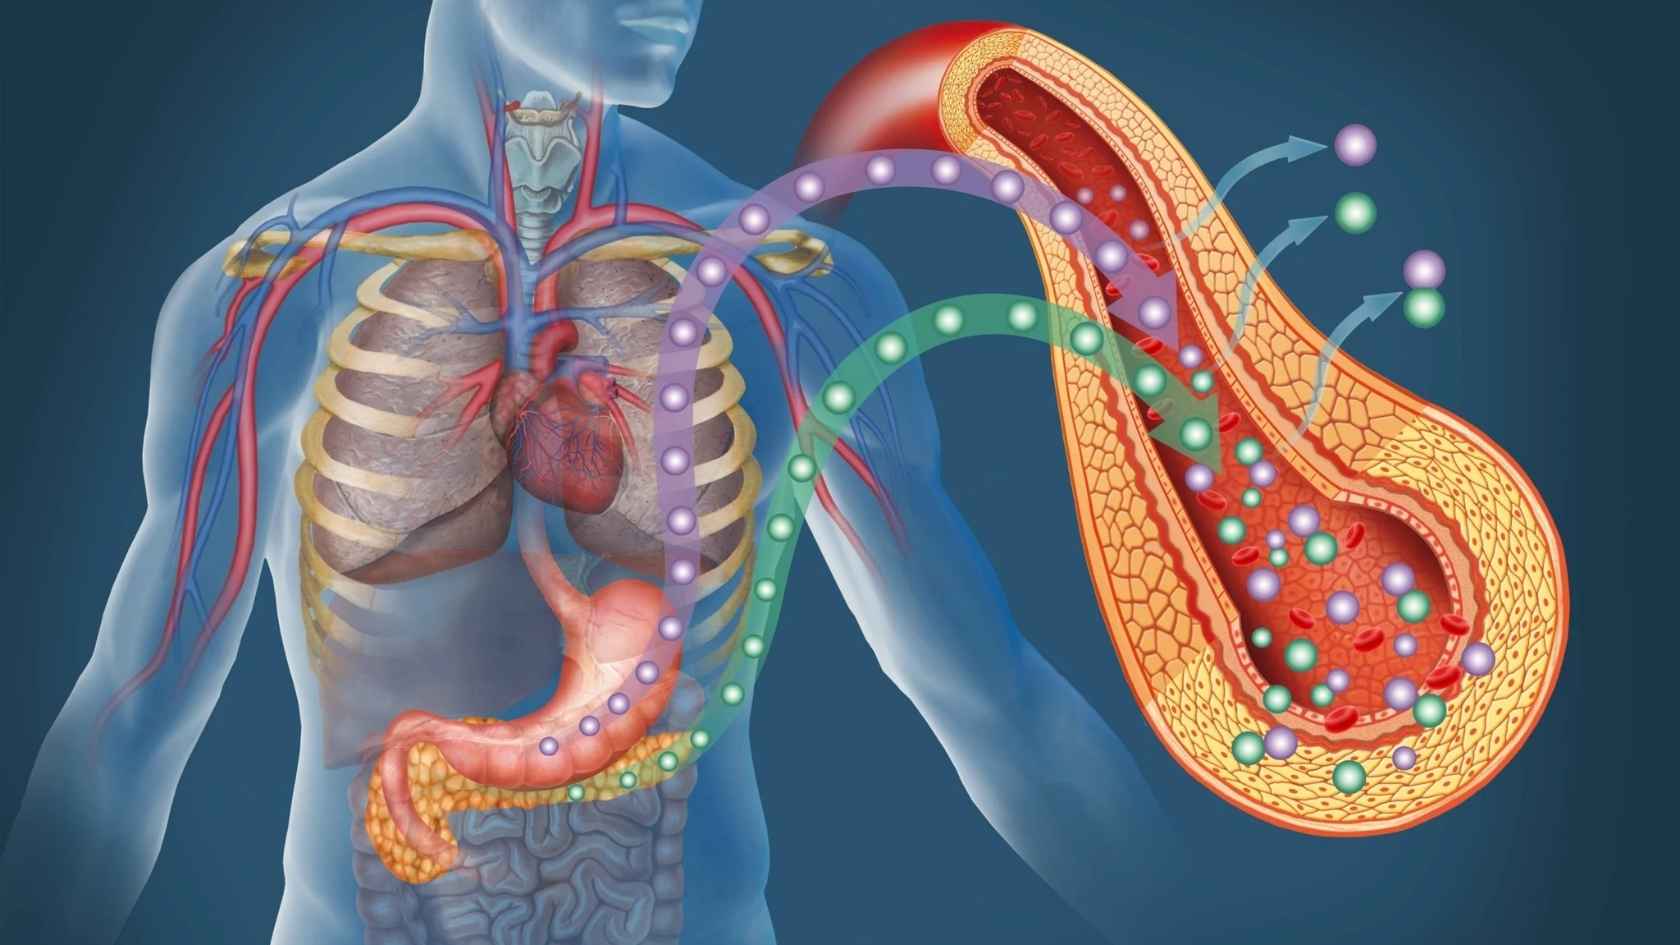

Metabolic means how your body processes food into energy.

Type 2 diabetes damages your body from within. It weakens insulin response, disrupts blood sugar control, harms organs, and creates a metabolic imbalance. Standard treatment manages glucose but ignores the metabolic stress damaging your pancreas, liver, nerves, and vessels.

Because these conditions are systemic, they need a systemic solution.

Ayurveda views health as an interconnected system that links metabolism, digestion, activity, rest, and organ function. Instead of treating symptoms in isolation, it supports the body’s natural regulatory processes to maintain stability.